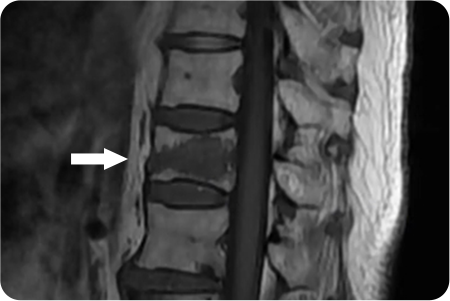

2

관절경하

척추관협착증 수술

1cm 내외 절개를 통해 내시경을 삽입해

신경을 압박하는 원인을 정확히 파악합니다.

두꺼워진 황색인대나 뼈 일부를 제거하여

신경이 지나가는 공간을 넓혀줍니다.